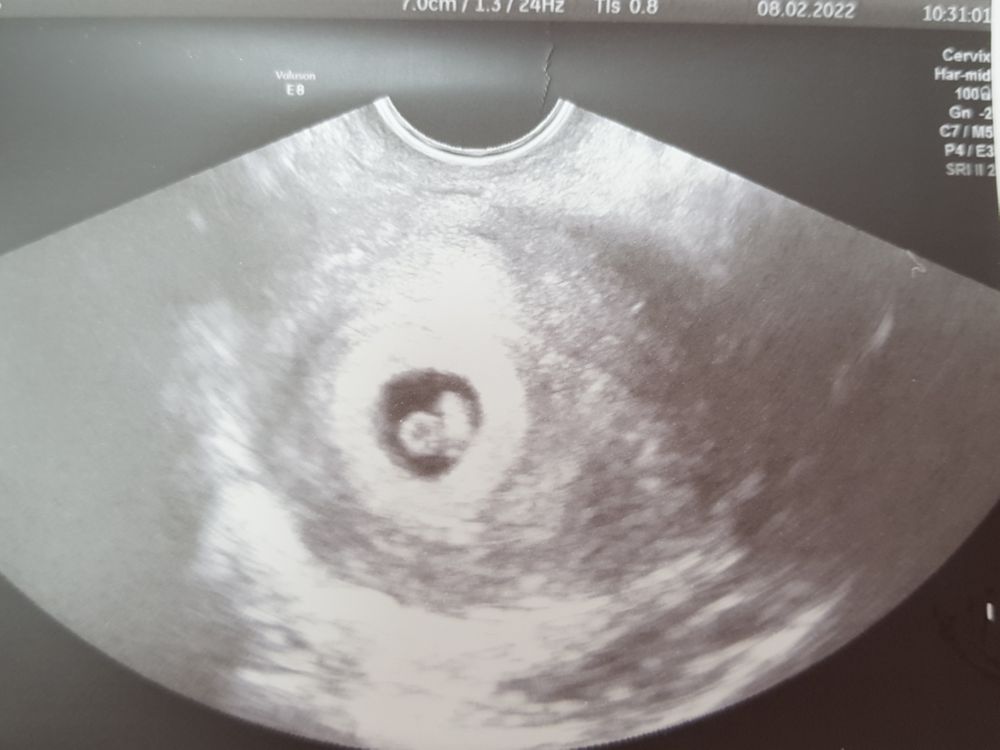

Новости с полей 28 ДПП узи

Я БЕРЕМЕННА !Девочки все у нас отлично.

ПЯ 15.1 мм

ЖМ 4.1

КТР 7.3 мм

Сердечко 💓💓💓 +

Я так счастлива, хочется всему миру рассказать, что я беременна!!!! И все это происходит со мной. У меня сегодня 28 дпп, это 6 недель и 4 дня. В УЗИ написано просто 6-7 недель.